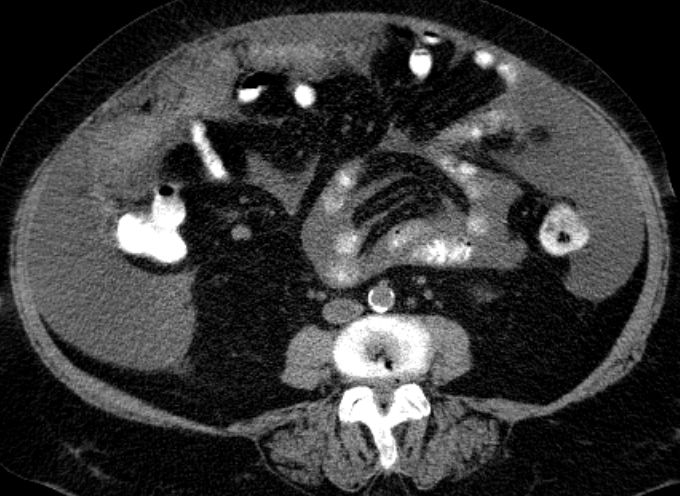

73-jährige Frau mit Ascites, Pleuraerguss links und Unterbauchtumor.  Das Netz ist komplett in einen Omental-Cake umgewandelt. An der Zwerchfellkuppe miliare Tumoraussaat.

Beide Adnexe in knapp kindskopfgroße blumenkohlartige Tumoren umgewandelt.

Im Douglas finden sich pararektal mehrere bis zu pflaumengroße Tumorknoten.